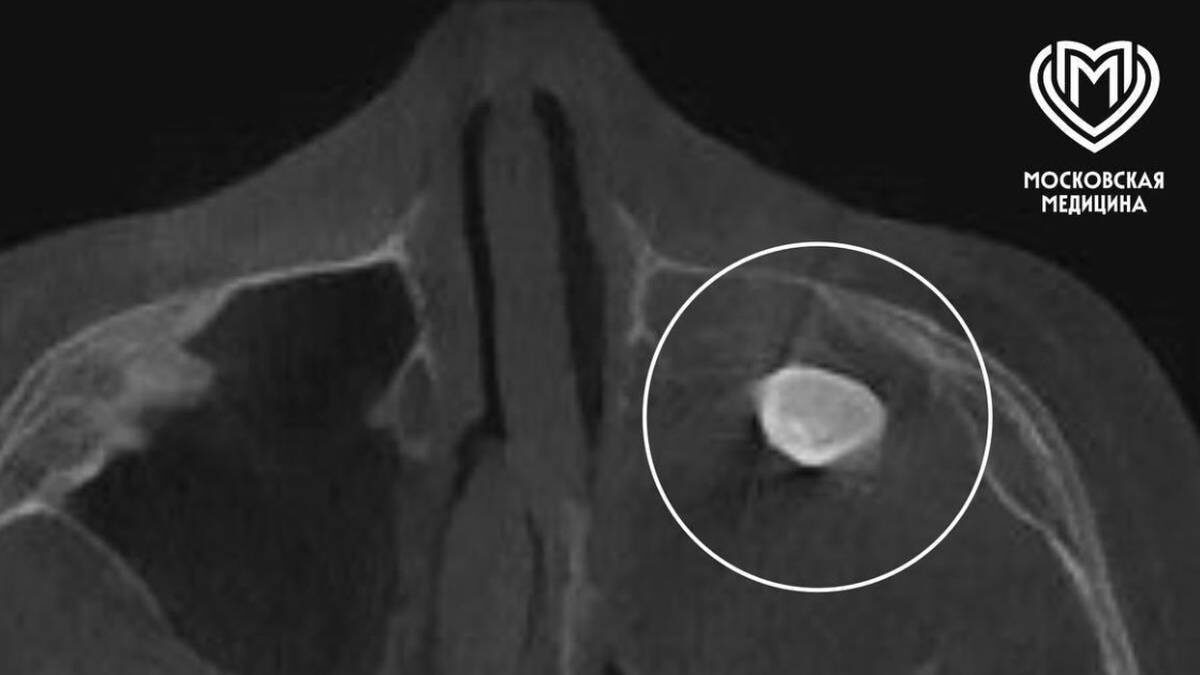

Московские врачи удалили подростку зуб, выросший в носу

Фото: Telegram / Московская медицина

— Мальчику нужно было провести операцию по Колдуэллу-Люку. Сделав разрез, врачи обнаружили новообразование, внутри которого и находился зуб, — добавили в Telegram-канале ведомства.